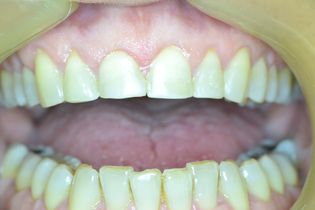

This 14-years old patient had brown stains on her enamel since birth.

The shape of her central incisors was also affected.

We performed two composite resin veneers in a single appointment, without anesthesia or tooth grinding and restored her smile back.